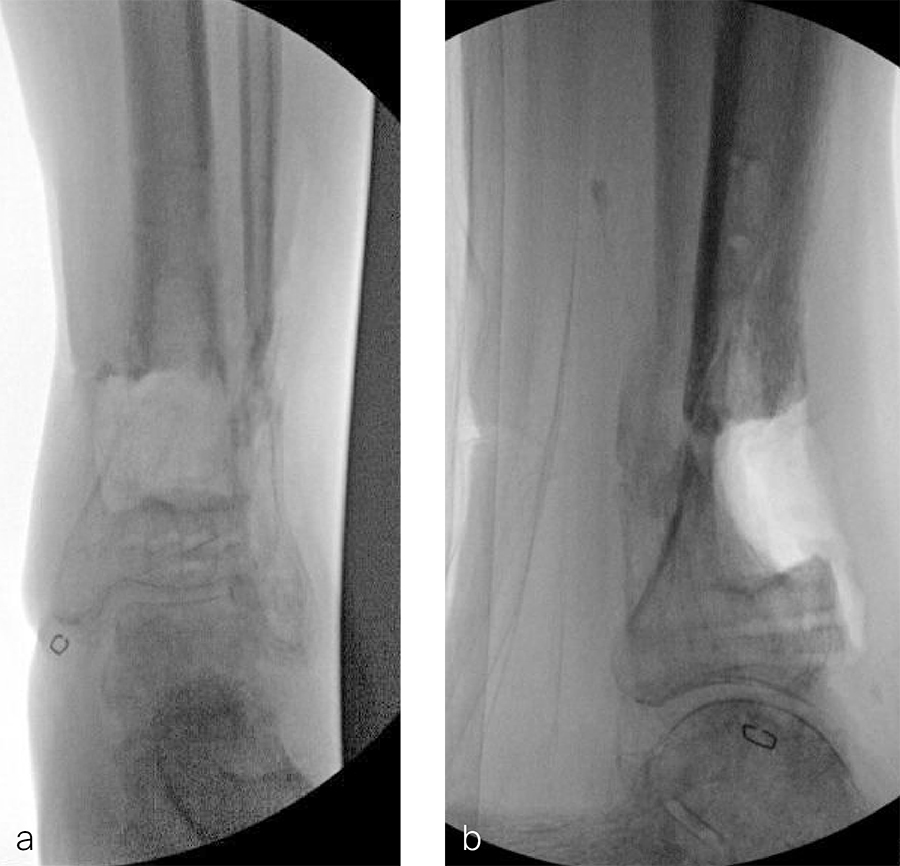

Two months later, the patient had a staged cement spacer removal and hardware removal followed by a new spacer placement (Fig 4). When microbiological cultures were negative for 5 days he was taken to the OR for definitive fixation and bone grafting. RIA bone graft from the ipsilateral femur was taken, a new anterior lateral plate was placed with an adjunct IM nail (and angle stable screws) as the distal plafond was now one articular block (Fig 5).

The patient has been followed up monthly for more than 5 months and has shown continued consolidation of the bone defect (Fig 6). Furthermore, he is weight bearing as tolerated without significant pain. The leg lengths are equal and the range of motion at the ankle is 10/25 dorsiflexion/plantarflexion. He has mild pain over the ankle joint but no pain at the fracture site.